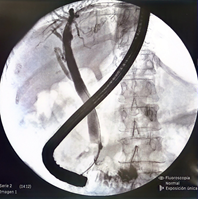

En consecuencia, se realiza una segunda donde se observa dilatación de la vía biliar extrahepática secundaria a papila intradiverticular, se realiza esfinterotomia por lo que se coloca prótesis biliar plástica de 10 Fr x 10 cm, corroborando su ubicación por fluoroscopia. (Figura 2 y 3)